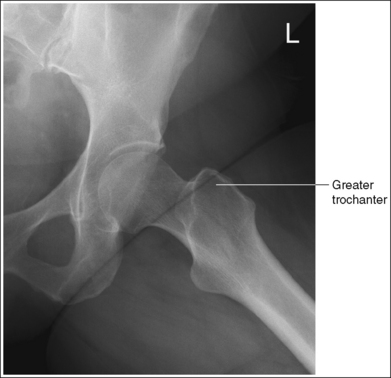

• Poor distal femur elevation. If the knee and hip are not flexed enough to place the femur at this angle with the imaging table, the greater trochanter is demonstrated laterally, as it is on an AP projection (see Images 7 and 8). If the knee and hip are flexed too much, placing the femur at an angle greater than 60 to 70 degrees with the imaging table, the greater trochanter is demonstrated medially (see Image 9). The greater trochanter is also demonstrated medially, as shown in Image 9, when the foot and ankle of the affected leg are elevated and placed on top of the unaffected leg. This positioning causes the femur to rotate externally. The foot of the affected leg should remain resting on the imaging table.

IMAGE 8

The greater trochanter is positioned laterally. The patient's knee was not flexed enough to align the femur at a 60- to 70-degree angle with the imaging table (20 to 30 degrees from vertical). The proximal greater trochanter is visible at about the same transverse level as the femoral head, indicating too much femur abduction.

Decrease the knee flexion until the femur is aligned at a 60- to 70-degree angle with the imaging table, as shown in Figure 7-11.